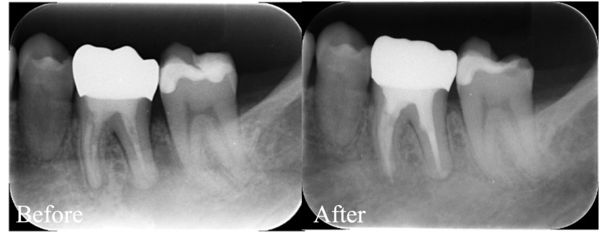

【症例】根管治療の成功率を下げる「落とし穴」

自由が丘の歯医者・歯科「三好歯科 自由が丘」は駅徒歩1分、土日診療、ご相談に応じて診療時間外でも対応する通いやすい歯医者です。今回は、他院で治療された歯が感染し、その治療を行うマイクロエンドの症例にな…